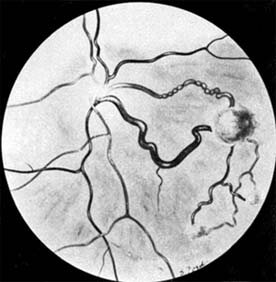

Enucleation is the treatment of choice for large retinoblastomas. Eyes with smaller tumors can be effectively treated with plaque or external beam radiotherapy (Figure 10-34), cryotherapy, or photocoagulation. Chemotherapy is being used to reduce the size of large tumors prior to other types of therapy and occasionally as the sole form of therapy. It is also used to treat tumors that have extended into the brain, orbit, or distally and may be used after enucleation in patients at high risk for such widespread disease.

Figure 10-34

Figure 10-34: Retinoblastoma after radiotherapy.